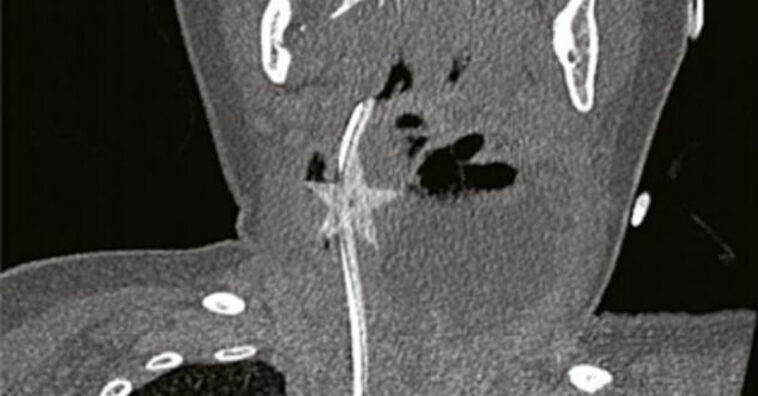

Porém, 6 dias depois, ela ainda apresentava os mesmos sintomas e assim os médicos decidiram fazer um exame de imagem. Nele, surpreenderam-se ao encontrar uma estrela de Natal alojada em sua garganta. Imediatamente, ela foi levada para a sala de cirurgia, onde o objeto foi retirado com sucesso, ficando tudo bem com a bebê.